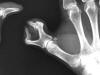

Carpo normal

Artritis psoriásica y falange bífida.

Falange distal de dedo 1º de mano, bífida.